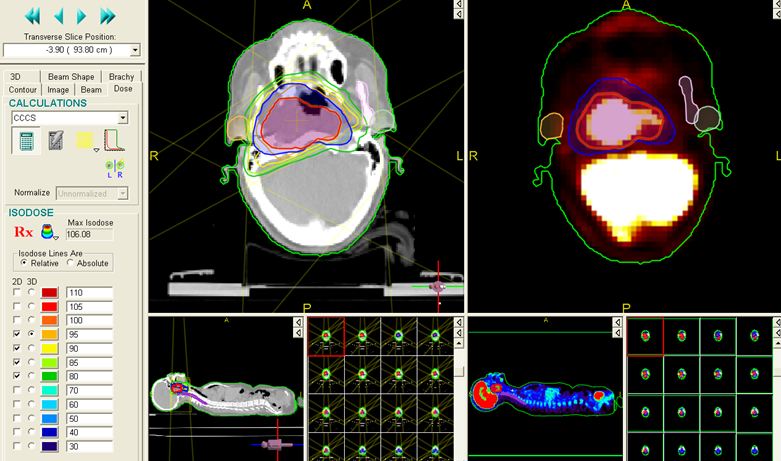

* Sau khi chụp, toàn bộ hình ảnh mô phỏng sẽ được chuyển sang hệ máy tính lập kế hoạch điều trị -TPS qua cổng DICOM. Các bác sỹ xạ trị xác định các thể tích xạ trị: GTV (thể tích khối u thô) trên hình CT mô phỏng, CTV (thể tích bia lâm sàng) và PTV (thể tích lập kế hoạch xạ trị). Trên hình PET/CT mô phỏng sẽ xác định được BTV (thể tích khối u sinh học) và các cơ quan cần bảo vệ (hình 3).

Trên hình CT mô phỏng xác định được:

-         GTV (màu vàng)

-         CTV (màu xanh lá cây)

-         PTV (màu đỏ)

Trên hình PET/CT mô phỏng xác định được:

-         BTV (màu vàng)

Hình 3: Các thể tích xạ trị được vẽ trên hình CT và PET/CT mô phỏng.

Tại Trung tâm Y học hạt nhân và Ung bướu Bệnh viện Bạch Mai lần đầu tiên tại Việt Nam ứng dụng chụp PET/CT mô phỏng và lập kế hoạch xạ trị cho các bệnh nhân ung thư các loại trong đó có ung thư vòm họng từ năm 2009. Đến nay có hàng trăm bệnh nhân được điều trị thành công với kỹ thuật này. Hiện tại chúng tôi đã có được phần mềm lập kế hoạch xạ trị 3D và IMRT trên hình ảnh CT mô phỏng và PET/CT mô phỏng bằng tiếng Việt, tạo thuận lợi cho các nhà xạ trị lập kế hoạch tốt hơn (hình 4 - 10)

Hình 4: Xác định BTV (u và hạch cổ) trên hình PET/CT mô phỏng bằng phần mềm tiếng Việt.

Hình 5: Đặt các trường chiếu, các segments trong kế hoạch xạ trị 3D

Hình 6: Đặt các trường chiếu, segments và tính liều trong kế hoạch xạ trị IMRT.